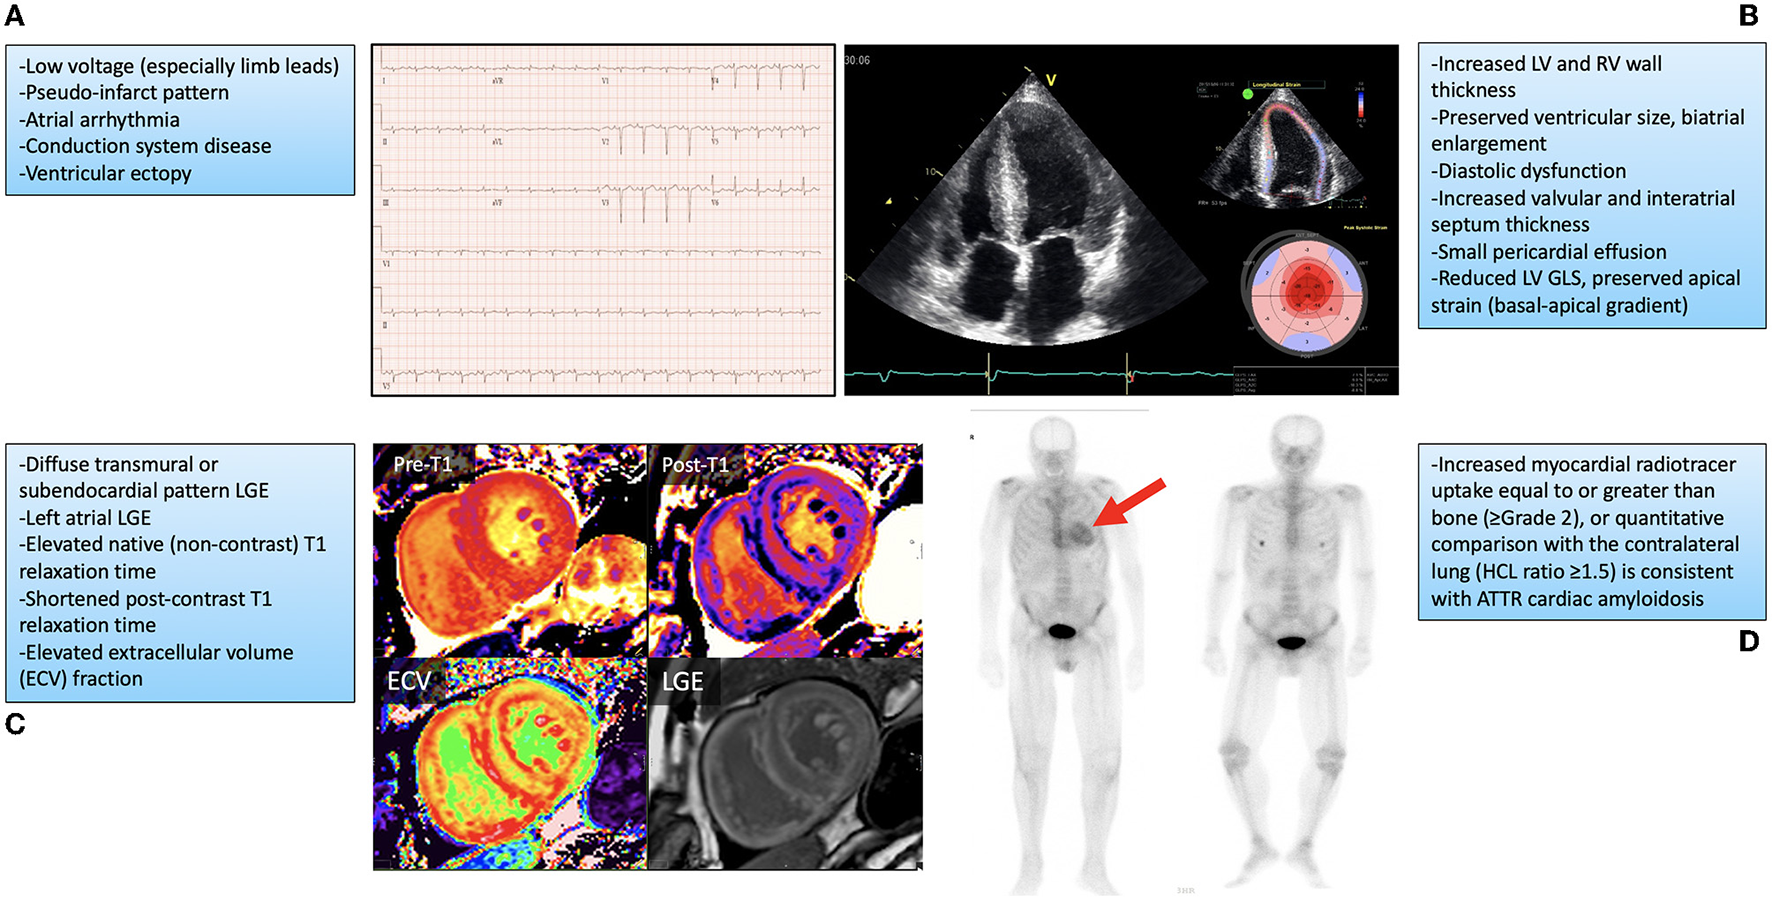

Although cardiac manifestations may predominate for many patients, ATTR is a multisystem disease that includes somatic and autonomic neurologic, musculoskeletal, gastrointestinal and ophthalmologic symptoms, among others (2, 13, 14). Many disease manifestations may mimic or exacerbate other age-related disorders, which can make clinical recognition difficult in older patients, particular in the early stages. Heart failure remains the most common clinical presentation for ATTR-CM patients (2). In many patients this is slowly progressive and initially manifests as exercise intolerance and worsening dyspnea on exertion, advancing to overt biventricular heart failure symptoms, including right heart failure causing peripheral edema, fatigue, early satiety and abdominal bloating, and left heart failure causing pulmonary congestion, orthopnea and paroxysmal nocturnal dyspnea. In early stages, older patients may not seek medical attention and attribute their symptoms to aging. As symptoms progress and patients seek medical attention, clinicians may not recognize ATTR-CM, either because of limited awareness or a lack of other typical ‘red-flag' findings associated with more advanced stages of this disease (15). Patients may initially be mis-diagnosed with HFpEF, a common disorder that represents approximately half of all heart failure in the community (16, 17). ATTR-CM predominantly presents with preserved LV EF (although EF can become reduced in later stages), making differentiation of these two diseases difficult (4). Phenotypic similarities between ATTR-CM and HFpEF present on cardiac imaging assessment may also include increased LV wall thickness, diastolic dysfunction, and atrial enlargement. Differentiating features may include the presence of increased right ventricular wall thickness which would be more associated with ATTR-CM, along with findings more specific to ATTR-CM by advanced imaging techniques such as: reduced global but preserved apical LV longitudinal systolic strain by speckle-tracking echocardiography, diffuse subendocardial or transmural late-gadolinium enhancement and increased native T1-mapping time and post-contrast extracellular volume quantification using cardiac magnetic resonance imaging (Figure 1) (8, 18–22).

Figure 1

Findings on cardiovascular investigations associated with cardiac amyloidosis along with representative examples. (A) Typical electrocardiogram findings and representative example. (B) Echocardiogram findings, with imaging from the apical 4-chamber view (left image) showing biventricular wall thickening, preserved ventricular size, valve thickening, and biatrial enlargement, with longitudinal strain measurement on speckle-tracking echocardiography (top right) showing preserved apical strain with impaired basal and middle segment values (bottom right). (C) Cardiovascular magnetic resonance imaging findings with representative examples showing diffuse elevation in native T1 (no contrast; Pre-T1) mapping (top left), reduction in post contrast T1 (Post-T1) mapping (top right), increased extracellular volume (ECV; bottom left), and subendocardial late gadolinium enhancement (LGE) of the left and right ventricles (bottom right). (D) 99 mTc-pyrophosphate nuclear scintigraphy showing increased myocardial uptake in a patient with transthyretin cardiac amyloidosis (red arrow, left panel) and absent myocardial uptake in a patient without this diagnosis (right panel). GLS, global longitudinal strain; HCL, heart/contralateral lung ratio; LV, left ventricular; RV, right ventricular. Fine et al., (4).

Considering the challenges in recognizing ATTR-CM, an approach suggested by current literature includes ATTR-CM screening in patients presenting with multiple manifestations of disease, such as patients presenting with heart failure and peripheral neuropathy, autonomic dysfunction, or spinal stenosis, for example (2–4, 14, 15). Another suggestion is screening patients with unexplained increased LV wall thickness on imaging whose demographic profile put them at risk for ATTR-CM, including their age and ethnicity (4). Many patients with ATTR-CM are initially recognized following screening cardiovascular investigations for evaluation of heart failure or arrhythmia symptoms. Typically, this would include increased LV wall thickness with preserved biventricular chamber size on echocardiography or cardiovascular magnetic resonance imaging (CMR), and elevated cardiac biomarkers including troponin and B-type natriuretic peptide or amio-terminal pro-B-type natriuretic protein (BNP/NTproBNP) (2–4). Other common ATTR-CM findings on cardiovascular investigations are described in Figure 1. When cardiac amyloidosis is suspected based upon either clinical presentation or investigation findings, an important next step is to exclude AL (light chain) amyloidosis by testing for the presence of monoclonal protein in the serum and urine through electrophoresis and free light chain assay testing. The presence of monoclonal protein may suggest a plasma cell dyscrasia and trigger referral to a hematologist or oncologist for further testing (4). If AL amyloidosis is excluded, the recommended approach to non-invasive confirmation of ATTR-CM diagnosis is to perform technetium nuclear scintigraphy with bone-seeking radiotracer (including pyrophosphate, PYP and 3,3-diphosphono-1,2-propanodicarboxylic acid (DPD). If technetium nuclear scintigraphy is either unavailable or results are equivocal then cardiac biopsy should be performed. Once ATTR-CM is diagnosed, genetic testing should be performed to differentiate the wild-type from hereditary subtype (2–4).